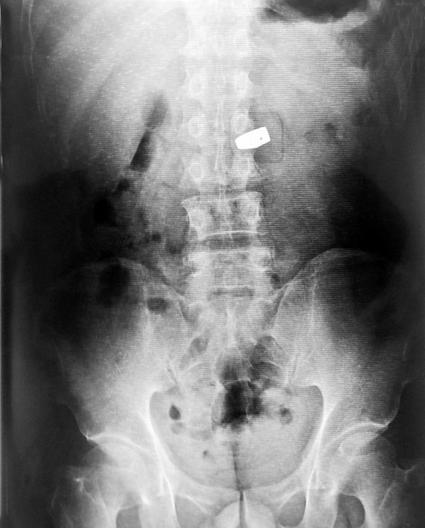

X光图片

一名中國女游客秦某,在泰國曼谷珠寶展上趁人不備,把一顆價值200萬人民幣的6克拉鉆石囫圇吞下。警方通過X光,找到位于其大腸中的鉆石,并讓醫生使用腸鏡等器械,將鉆石從該女子的腸中取出。

事后,警察在檢查護照時發現,該女子確系中國人。但是,值得注意的是,失竊的珠寶商也被一同抓了起來,因為涉嫌高價販賣假鉆——據悉,真鉆在X光下是無法被發現的。